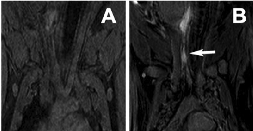

Pre-contrast (A) and Post-contrast (B) 3T MR image of inflammatory lesion induced at the dome of artificial aneurysm. RSNA ©

While the specific events leading to aneurysm rupture have yet to be fully elucidated, there is evidence to suggest that local inflammation may play a role in aneurysm instability. Using enzyme-sensitive substrate (di-5-HT-DPTAGd) MR signal amplification of myeloperoxidase (MPO), we seek to develop an experimental animal model of aneurysm inflammation using local injection of a pro-inflammatory mediator and image local MPO activity. We image MPO-mediated inflammation imaging signal that we proposed as a biomarker reflecting the aneurysm instability (Supported by NINDS exploratory grants).